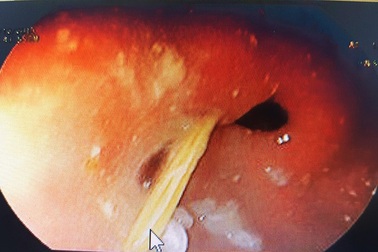

Quảng Bình: Bị đâm thủng dạ dày vì vô tình nuốt tăm tre vào bụngTrong lúc ngậm tăm, một thanh niên đã vô tình nuốt tăm tre nhọn 2 đầu vào bụng, gây thủng dạ dày. Chiếc tăm này đã được bác sĩ nội soi, gắp ra ngoài.